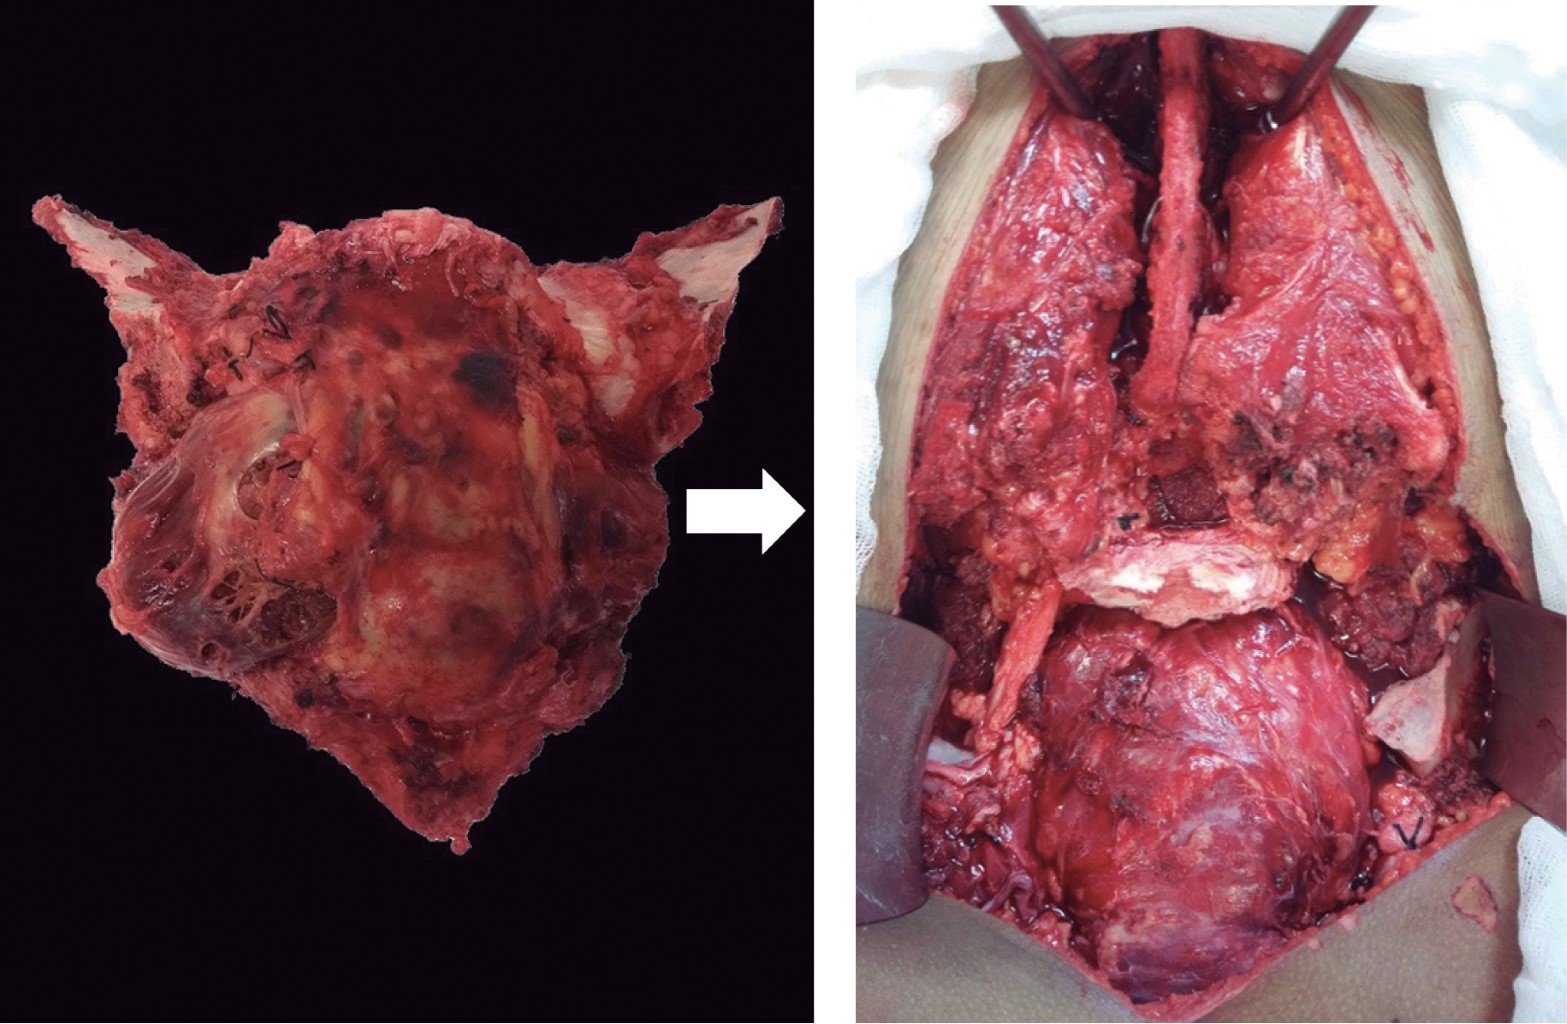

En bloc resection with adequate margins has provided a chance for cure of primary sacral tumors, however, high sacral lesions are challenging because of the complexity of the surgical approach, risk of exsanguination, and morbidities. Because massive blood loss has occurred frequently, two-stage sequential surgery has been used.43 Low sacral tumors are approached posteriorly, and high sacral tumors are approached by combined anterior and posterior incisions1 (Figure 4).

Extirpation of sacral tumors often leads to large and complicated defects with deep cavities, exposed viscera, and loss of the sacrum, bowel and bladder control, sexual function and weight-bearing joints.19 Other difficulties encountered after sacrectomies are musculocutaneous reconstruction to cover the generated defect. Additionally, postoperative radiotherapy is often necessary, which increases the likelihood of wound complications in the postoperative period.3,45 A prolonged surgical time is related with a higher risk of deep infection.32 Postoperative neurologic deficits may be acceptable, given the dreadful outcome of recurrent disease.43

Figure 4